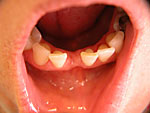

Implantation – Patientenbeispiel 1: